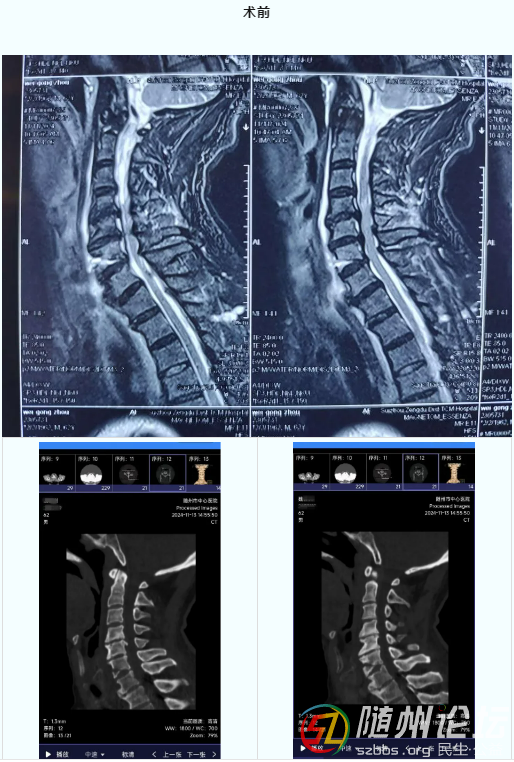

事發(fā)當(dāng)日,魏先生因突發(fā)車禍,導(dǎo)致全身多處損傷,四肢麻木無(wú)力,軀干部緊束感。在當(dāng)?shù)蒯t(yī)院行MRI檢查提示:頸6骨折,頸4-6髓內(nèi)高信號(hào),隨即由急診120轉(zhuǎn)入我院。創(chuàng)傷中心團(tuán)隊(duì)立刻啟動(dòng),頸部固定牢固后迅速完善頸椎CT檢查。曹輔國(guó)、汪群博副主任閱片發(fā)現(xiàn),患者外院頸椎MRI提示:頸6椎體骨折,脊髓高信號(hào),本院CT提示:椎體前方及椎管內(nèi)骨質(zhì)增生明顯。分析原因考慮患者既往有脊椎病史,本次外傷后造成頸椎骨折,并脊髓壓迫癥狀加重,診斷為頸椎骨折并脊髓損傷。立即給予甘露醇脫水、激素沖擊治療保護(hù)脊髓。同時(shí)與家屬溝通病情安排手術(shù)。

術(shù)前